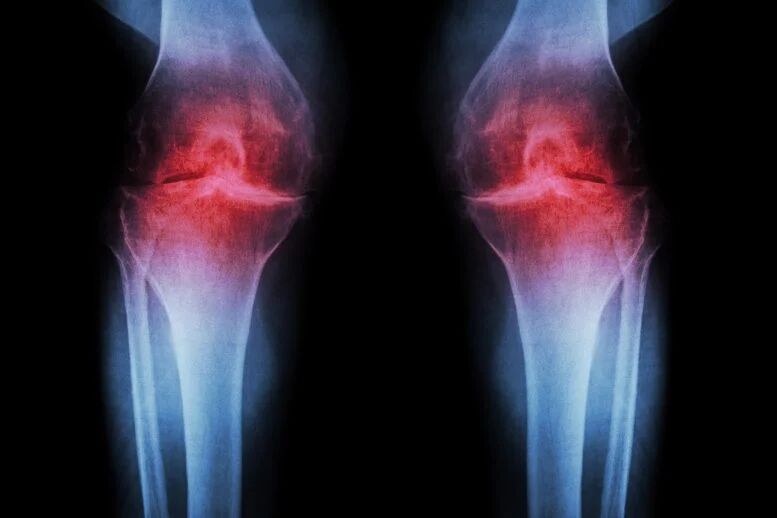

تهران- مگ مهر- دانشمندان با کشف یک روش درمانی انقلابی اعلام کردند بهزودی میتوان غضروف فرسوده زانو را با یک تزریق یا حتی یک قرص بازسازی کرد که از بروز آرتروز پس از آسیبهای ورزشی مانند پارگی رباط صلیبی جلوگیری میکند.